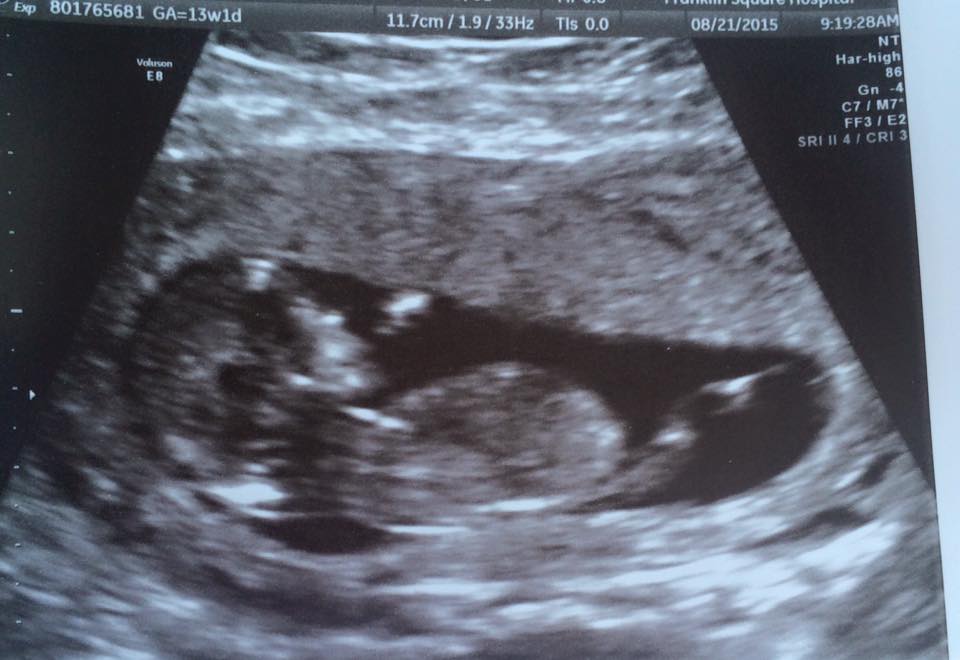

My husband and I are expecting our first baby, and we cannot wait to find out! We are going to have an elective ultrasound in two weeks, but I wanted to post my ultrasound here to get everyone's thoughts! We will be so happy either way! This is from my ultrasound at 13 weeks and 1 day. The baby was wiggling around a lot, but here is the clearest image I have.